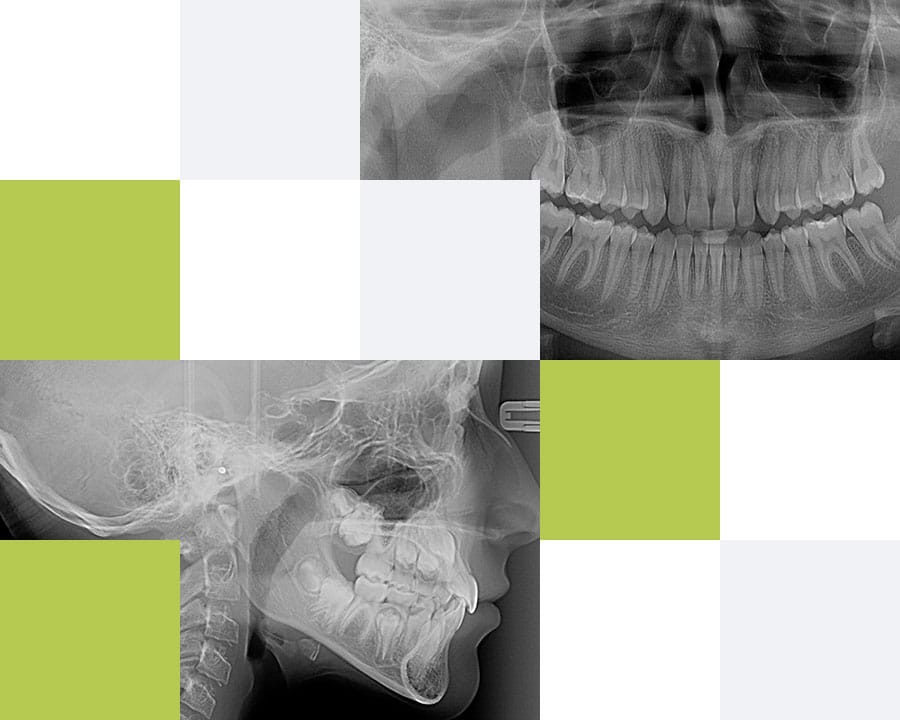

5. Teleradiografia de profil

Teleradiografia de profil este indicată atunci când se dorește aplicarea unui aparat ortodontic (pentru corectarea poziției dinților) sau corectarea profilului osos și a mușcăturii pacientului. Această radiografie evidențiază raportul dinților cu maxilarele și a maxilarelor cu oasele craniului pe care medicul ortodont le măsoară pentru a putea stabili diagnosticul și planul de tratament.

1. Radiografia digitală panoramică

Radiografia panoramică (Ortopantomografia) furnizează medicului o imagine de ansamblu a dentiției și a elementelor anatomice maxilo-faciale înconjurătoare. Această radiografie se realizează înainte de orice tratament stomatologic, astfel încât medicul să aibă o imagine completă a cazului pe care îl tratează, să evalueze posibile leziuni inflamatorii sau dinți neerupti, structura osoasă de susținere, articulațiile temporo-mandibulare, să vizualizeze molarii de minte, rapoartele dinților cu repere anatomice învecinate (nerv alveolar, sinus maxilar) sau posibile fracturi osoase maxilare sau mandibulare.